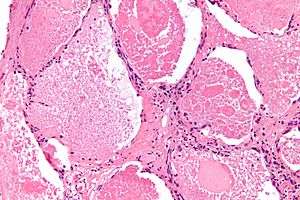

| Micrograph of pulmonary alveolar proteinosis, showing the characteristic airspace filling with focally dense globs referred to as chatter or dense bodies. H&E stain. | |

Microscopically, the distal air spaces are filled with a granular, eosinophilic material that is positive with the PAS stain and the PAS diastase stain. The main histomorphologic differential diagnosis is pulmonary edema, which does not have dense bodies.